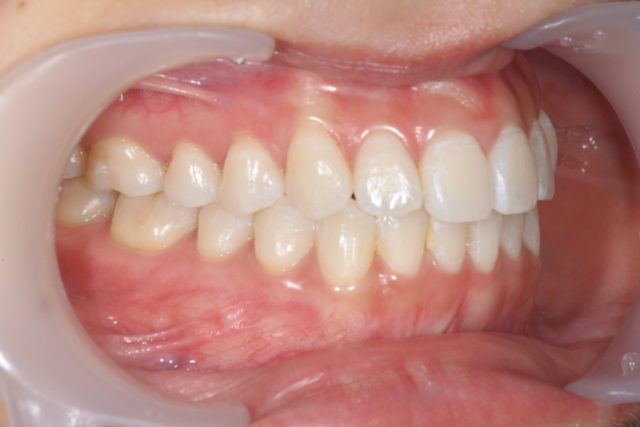

③お口を閉じたときの右側のお写真

ワイダーを引っ張って奥歯まで映しています。

右奥歯の頬側の汚れや歯茎の状態などを診ています。